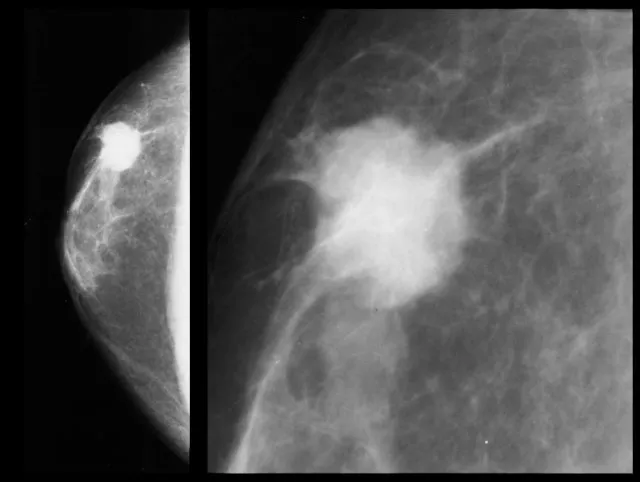

| Breast | 50-71 years | 3-yearly | Mammography (2 views) | Suspicious lesion (R4/R5) → 2-week wait |

✓ Breast screening: 50-71 years, 3-yearly mammography; R4/R5 lesions → urgent referral